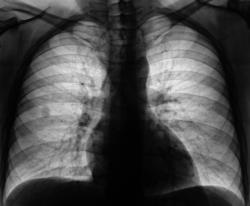

Произведено дообследование - рентгенография в прямой и правой боковой проекциях.

Обращает на себя внимание неоднородность структуры тени с отдельными участками точечного уплотнения. Решено провести линейную томографию в прямой проекции.

С учетом теневых характеристик данного образования предположительно выставлен диагноз "Гамартохондрома".

Ваше мнение коллеги?

Гамартома на первой позиции в ряде дифференцировки.

Интересная гамартома.